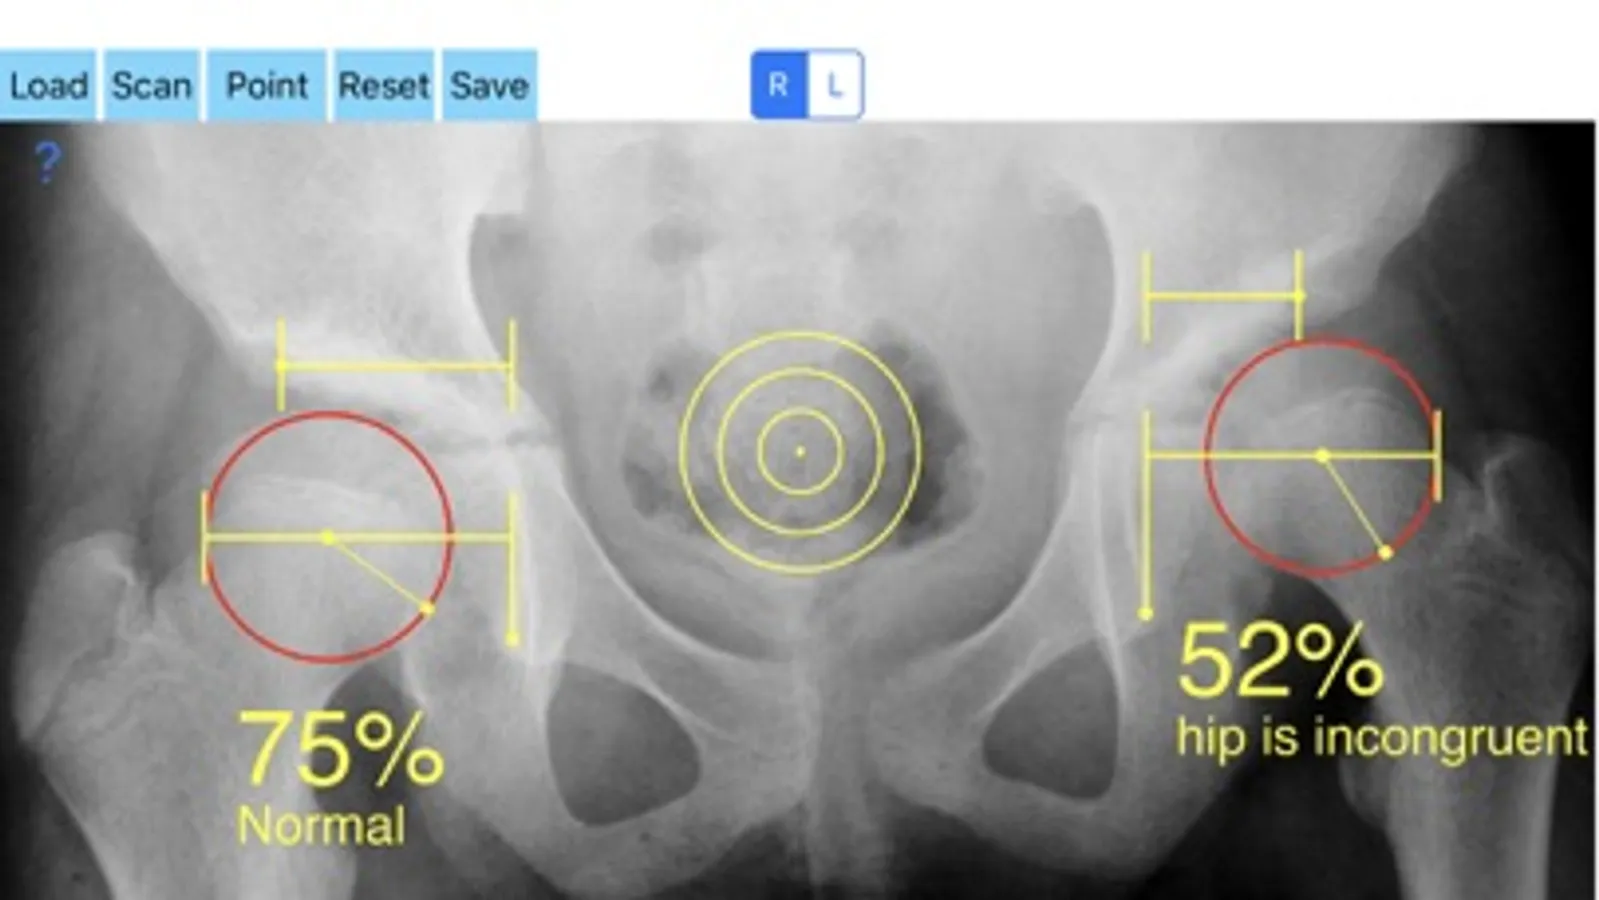

Treatment of incongruity is paramount importance because you have to address it early and the treatment of choice are usually corrective hip osteotomies. In order-from one hand to avert the natural course to the progression of secondary osteoarthritis (OA) and from another hand to avoid- in developing skeleton - to deteriorate more the hip dysplasia the congruity must be objectively and thoroughly evaluated especially at follow up of these procedures in both congruent and incongruent hips. Congruity between the femoral head and acetabulum is determined by the percentage of femoral head covered by the bony acetabulum. The congruity index (CI) is calculated (A/B- ratio converted to a percentage) by diving the (A) distance by the distance (B), where distance (A) is the distance between the teardrop to the lateral acetabular margin and (B) is the distance from the teardrop again to the lateral femoral head edge.

-Offers a very convenient way to determine the most accurate possibly way an objective value of congruity. By clicking three point at the x-ray picture on your iPhone screen and inserting the side the App calculates the congruity index (CI) which is the percentage of femoral head covered by the bony acetabulum. Congruity between the femoral head and acetabulum is expressed in percentage. Values of Coverage less than 75% is considered pathologic in another words the hip is incongruent